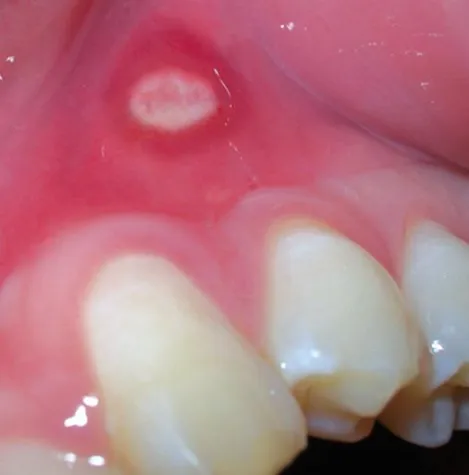

(openPR) Eine Aphthe ist eine schmerzhafte, von einem entzündlichen Randsaum umgebene Erosion der Schleimhaut des Zahnfleisches, der Mundhöhle, der Tonsillen oder der Zunge und in Einzelfällen auch anderer Schleimhäute, z.B. im Genitalbereich. Es handelt sich dabei um ein Ulcus mit weißlichem Fibrinbelag. Beim gleichzeitigen Auftreten mehrerer solcher Stellen im Rahmen einer Primärinfektion durch das Herpes-simplex-Virus spricht man vom Krankheitsbild der Mundfäule (Stomatitis aphthosa oder Gingivostomatitis herpetica). Treten Aphthen häufig wiederkehrend auf, spricht man von chronisch rezidivierender Aphthose.